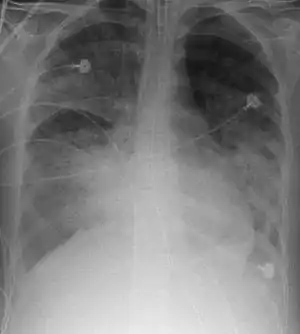

На рентгенографії легень видно двобічні дифузні інфільтрати, іноді — плевральний випіт. Такі ознаки неспецифічні й також характерні для кардіогенного набряку легень, що ускладнює диференціальну діагностику[15][16]. Комп'ютерна томографія показує негомогенну інфільтрацію легень у деяких відділах (у задньонижних відділах у лежачих хворих)[17]. Це пояснюється тим, що розподіл набряку легень залежить від сили тяжіння, а також тиском з боку розташованих вище набряклих відділів легень[18].